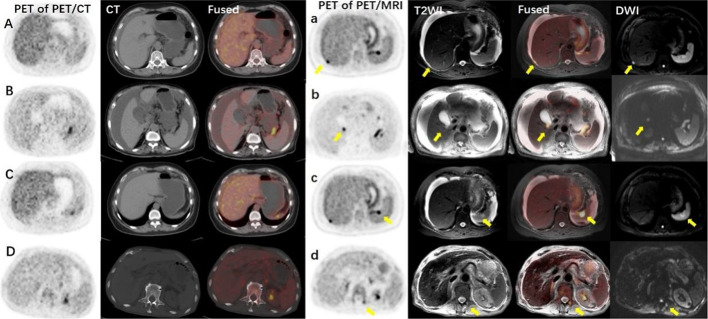

Background: Comparing to PET/CT, integrative PET/MRI imaging provides superior soft tissue resolution. This study aims to evaluate the added value of regional delayed 18F-FDG PET/MRI-assisted whole-body 18F-FDG PET/CT in diagnosing malignant ascites patients.

Results: The final diagnosis included 22 patients with ovarian cancer (n = 11), peritoneal cancer (n = 3), colon cancer (n = 2), liver cancer (n = 2), pancreatic cancer (n = 2), gastric cancer (n = 1), and fallopian tube cancer (n = 1). The diagnosis of the primary tumor using whole-body PET/CT was correct in 11 cases. Regional PET/MRI-assisted whole-body PET/CT diagnosis was correct in 18 cases, including 6 more cases of ovarian cancer and 1 more case of fallopian tube cancer. Among 4 cases that were not diagnosed correctly, 1 case had the primary tumor outside of the PET/MRI scan area, 2 cases were peritoneal cancer, and 1 case was colon cancer. The diagnostic accuracy of regional PET/MRI-assisted whole-body PET/CT was higher than PET/CT alone (81.8% vs. 50.0%, κ 2 = 5.14, p = 0.023). The primary tumor conspicuity score of PET/MRI was higher than PET/CT (3.67 ± 0.66 vs. 2.76 ± 0.94, P < 0.01). In the same scan area, more metastases were detected in PET/MRI than in PET/CT (156 vs. 86 in total, and 7.43 ± 5.17 vs. 4.10 ± 1.92 per patient, t = 3.89, P < 0.01). Lesion-to-background ratio in PET/MRI was higher than that in PET/CT (10.76 ± 5.16 vs. 6.56 ± 3.45, t = 13.02, P < 0.01).

Conclusion: Comparing to whole-body PET/CT alone, additional delayed regional PET/MRI with high soft tissue resolution is helpful in diagnosing the location of the primary tumor and identifying more metastases in patients with malignant ascites. Yet larger sample size in multicenter and prospective clinical researches is still needed.